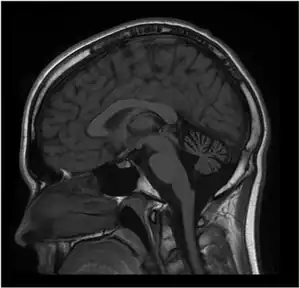

MRI of the brain. MRI was performed on Person 1 at 12 years of age. T1W1 sagittal image demonstrates prominent cerebellar atrophy involving superior and middle cerebellar folia. Axial images (not shown) revealed normal subcortical and cerebellar white matter. MR spectroscopy was normal (not shown). Repeat MRI imaging at 16 years old was unchanged (not shown). MRI of the brain (Person 2) showed a similar pattern but milder cerebellar atrophy (not shown).